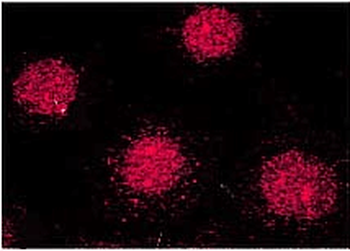

Anti-Cyclophilin A/PPIA Antibody [orb19174]

FC, ICC, IF, IHC, IHC-Fr, WB

Human, Mouse, Rat

Rabbit

Polyclonal

Unconjugated

10 μg, 100 μgCYPA Rabbit Polyclonal Antibody [orb100498]